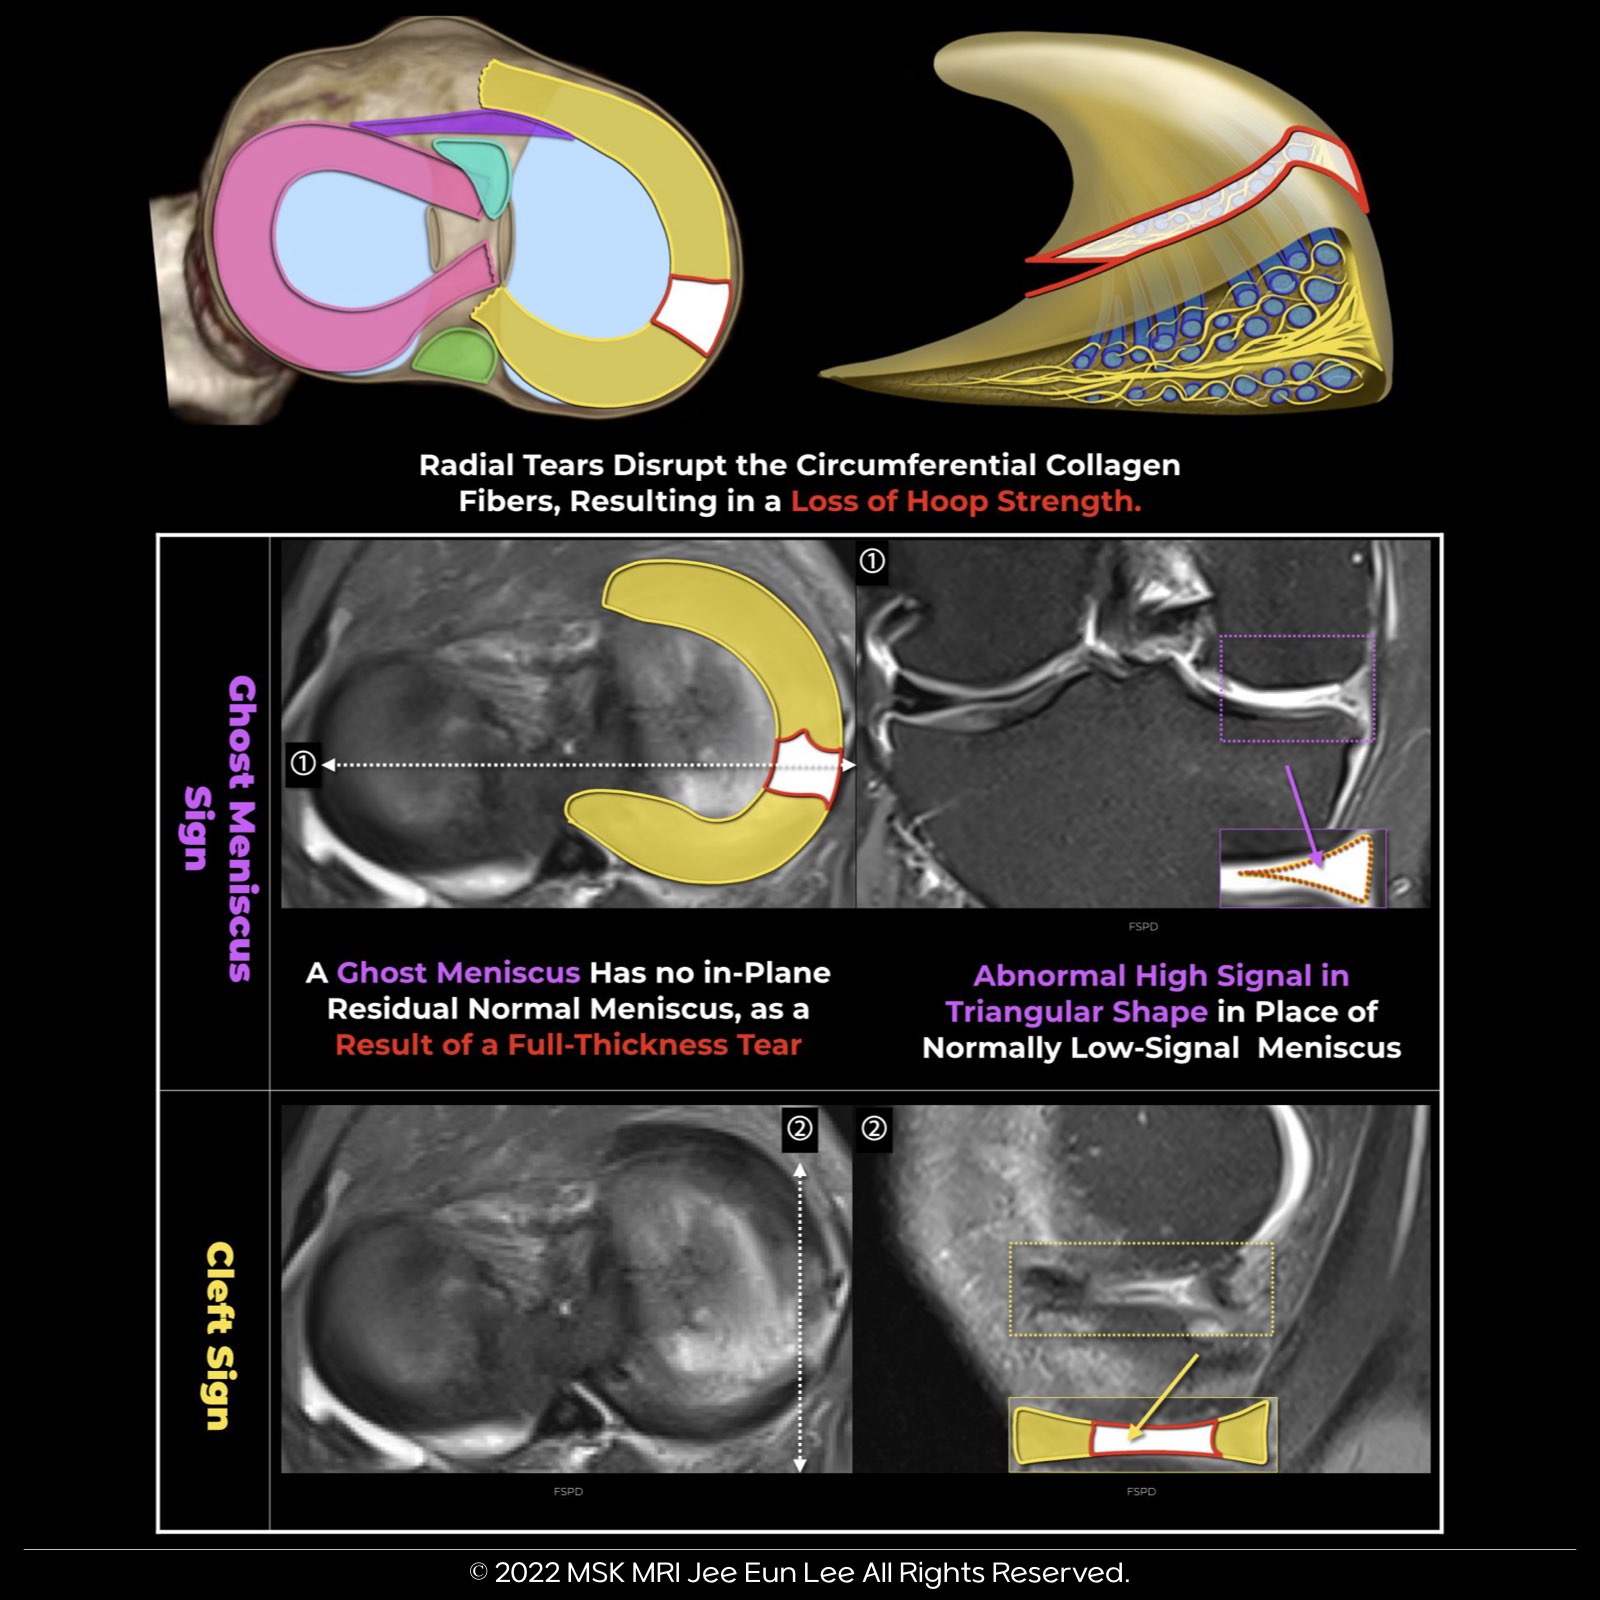

• Unlike horizontal and longitudinal tears, radial tears significantly disrupt meniscal hoop strength.

2. Ghost Meniscus Sign:

• High signal in place of the normally low signal posterior horn, suggesting a full-thickness tear.

3. Cleft Sign:

• Can indicate both longitudinal and radial tears, depending on the tear’s location relative to the imaging plane.